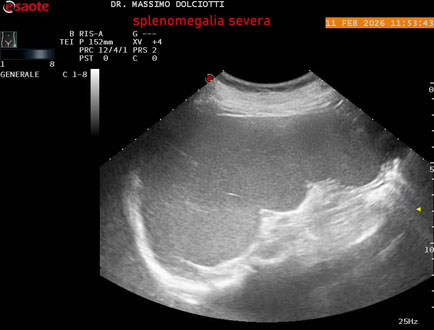

Data inserimento: 18/02/2026

Ecografia del: 11/02/2026

Strumento: Esaote MyLab Eight

Sonda: Conevx Multifrequenza 1-8 MHz

Età Paziente: F 68 anni

Motivazione dell'esame: follow up di splenomegalia.

Commento all'esame: le immagini ed il video documentano la milza con ecostruttura normale e morfovolumetria superiore alla norma, con diametro bipolare di 159 mm (v.n. 70-120 mm) ed area di sezione di 101 centimetri quadri (v.n. < 47 centimetri quadri).

Conclusioni: splenomegalia di severa entità (severe splenomegaly).